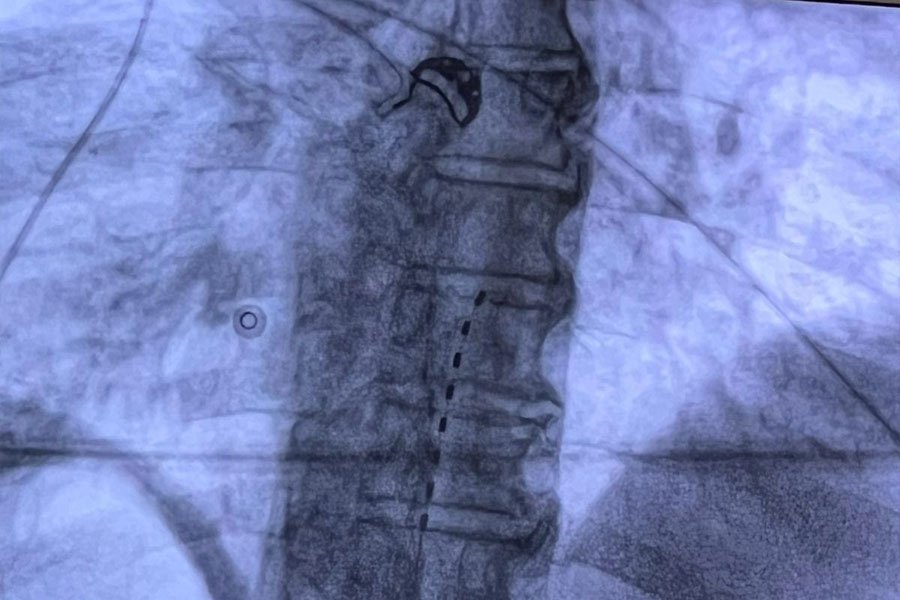

La Neurostimolazione Midollare o Spinal Cord Stimulation permette, attraverso sistemi impiantabili sotto cute costituiti da uno o più elettrodi e da un generatore d’impulsi (pacemaker), di creare un campo elettromagnetico attorno al midollo spinale, in grado di modulare la conduzione del dolore cronico.

Gli elettrodi vengono posizionati a livello dello spazio epidurale attraverso un’incisione percutanea in anestesia locale, quindi, collegati al generatore di impulsi che viene posizionato dentro una tasca sottocutanea in regione sovraglutea.